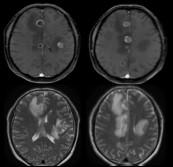

転移は脳のどこにでも起こるため、転移した場所に応じて様々な症状が出現します。ただし転移したがんが小さいうちは無症状のことも多く、検査で偶然に見つかる事もあります。がんが大きくなるとともに、周囲にむくみ(浮腫)を伴うことが多く見られ、頭痛やてんかん発作を引き起こすようになります。稀ではありますが、脳の周囲を循環する脊髄液の中に広く飛び散ると、髄腔播種またはがん性髄膜炎と呼ばれます。多くの場合にはMRIで脳転移が診断されます。